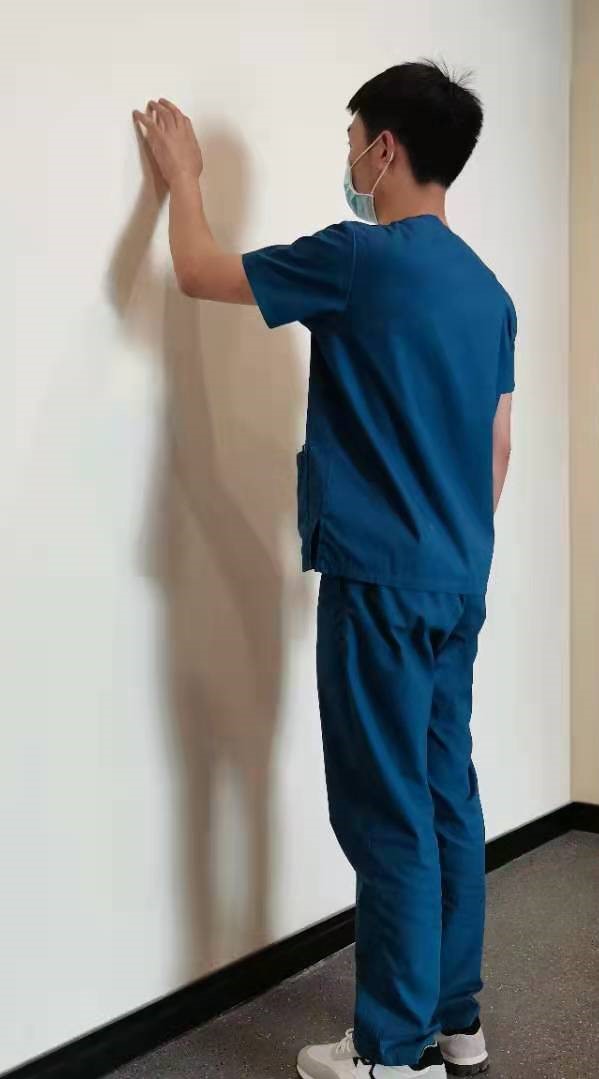

- 布骨医学科普:肩膀酸痛、活动受限怎么办?你可能有肩周炎了,那么肩周炎怎么预防和治疗呢? 布骨康复医疗中心 ,2021-05-08

- 肩周炎,全称为肩关节周围炎,是以肩关节疼痛和活动不便为主要症状的常见病症。好发年龄在50岁左右,也被称为五十肩。女性发病率略高于男性,多见于体力劳动者。如果得不到有效的治疗,不仅影响肩关节的功能活动,还会对生活产生极大影响。因此,找到肩周炎的最佳治疗方法时非常必要的。 首先让我们了解一下肩周炎.....